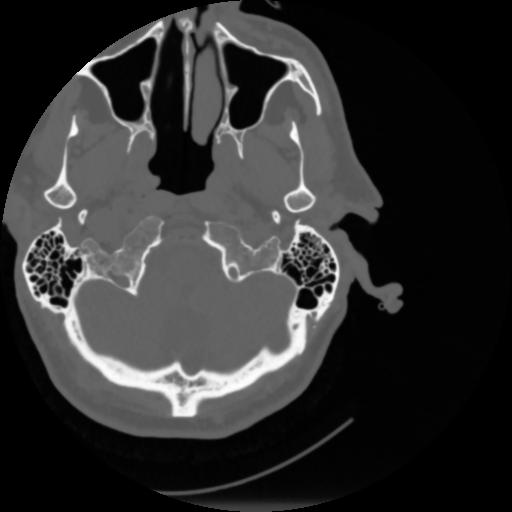

4 CEREBRO,,Vol,0.5,CEREBRO,,